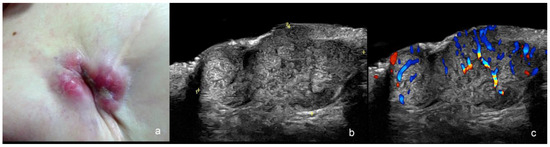

2. Melanoma

2.1. Primary Tumor

| Melanoma | hypoechoic, fusiform, flat or nodular, irregular or ill-defined borders | high degree |